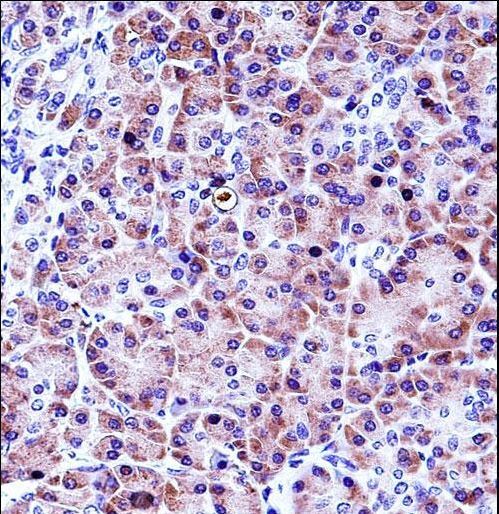

- Main image

- Experimental details

- CELA3A Antibody immunohistochemistry of formalin-fixed and paraffin-embedded human pancreas tissue followed by peroxidase-conjugated secondary antibody and DAB staining.